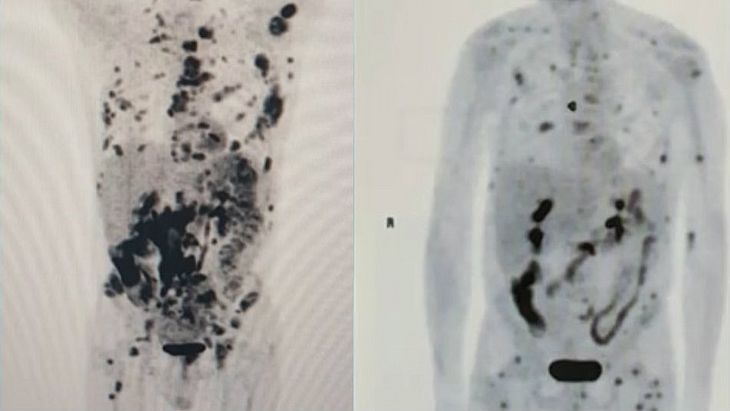

Exames feitos com pouco mais de um mês de diferença mostram o recuo de um linfoma em fase terminal em um paciente de 62 anos. Vamberto Luiz de Castro recebeu um tratamento inédito na América Latina, com uma técnica de terapia genética descoberta no exterior e conhecida como CART-Cell. As informações são do G1.

No início de setembro, segundo a publicação, o corpo do mineiro estava tomado por tumores, mas, nesta semana, a maioria já desapareceu. Segundo os médicos, isso é um indicativo da evolução da terapia. Para pesquisadores do Centro de Terapia Celular (CTC-Fapesp-USP), ligado ao Hospital das Clínicas de Ribeirão Preto, Vamberto está praticamente livre da doença.

Para os especialistas, porém, é difícil falar em cura porque o diagnóstico final só poderá ser dado após cinco anos de acompanhamento. Os exames apontam, segundo eles, a “remissão do câncer”.